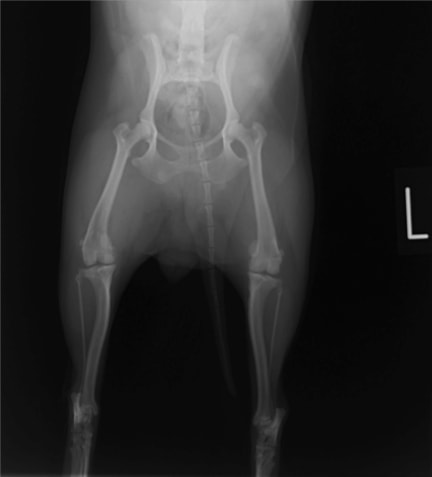

■ 症例20 ポメラニアン 8ヶ月 1.8kg

左右膝蓋骨脱臼 グレードⅢ

2ヶ月前から間欠的跛行が認められ、両膝の膝蓋骨脱臼整復術を行った。

手技は縫工筋及び内側広筋の解放、脛骨粗面の外側転位、滑車ブロック形造溝術、内外側関節包の縫縮を選択し実施した。

右側の膝蓋骨脱臼は上記手技で整復されたものの、左側はそれのみでは膝蓋骨が浮く様子が認められた。その為、PDS縫合糸にて膝蓋靱帯を1糸のみ縫合し、靱帯の縫縮を行った。

膝蓋骨脱臼は膝関節における膝蓋骨の内外側の脱臼と定義されるが、時として単純な内外の脱臼ではなく、膝蓋骨が大きく前方に浮き上がるように脱臼する場合がある。特にトイプードルやポメラニアンといった犬種に多く認められる。

内側脱臼に加えて前方への浮き上がりを矯正する為に、従来より脛骨粗面転移により膝蓋靭帯を外方と下方に引っ張り、固定する方法を選択する。膝蓋骨の前方への浮き上がりが軽度の場合は、従来法ではなく関節包の縫縮で対応していた。しかし、一部の症例で膝蓋骨の動きが悪くなり伸展機構が円滑に機能せずロボット様歩行になるケースがあった。

その為、膝蓋靭帯自体を縫縮する方法を採用した。この方法により、膝関節の伸展機構を妨げず膝蓋骨の軽度の浮きを矯正することが可能となった。

本症例の経過は良好である